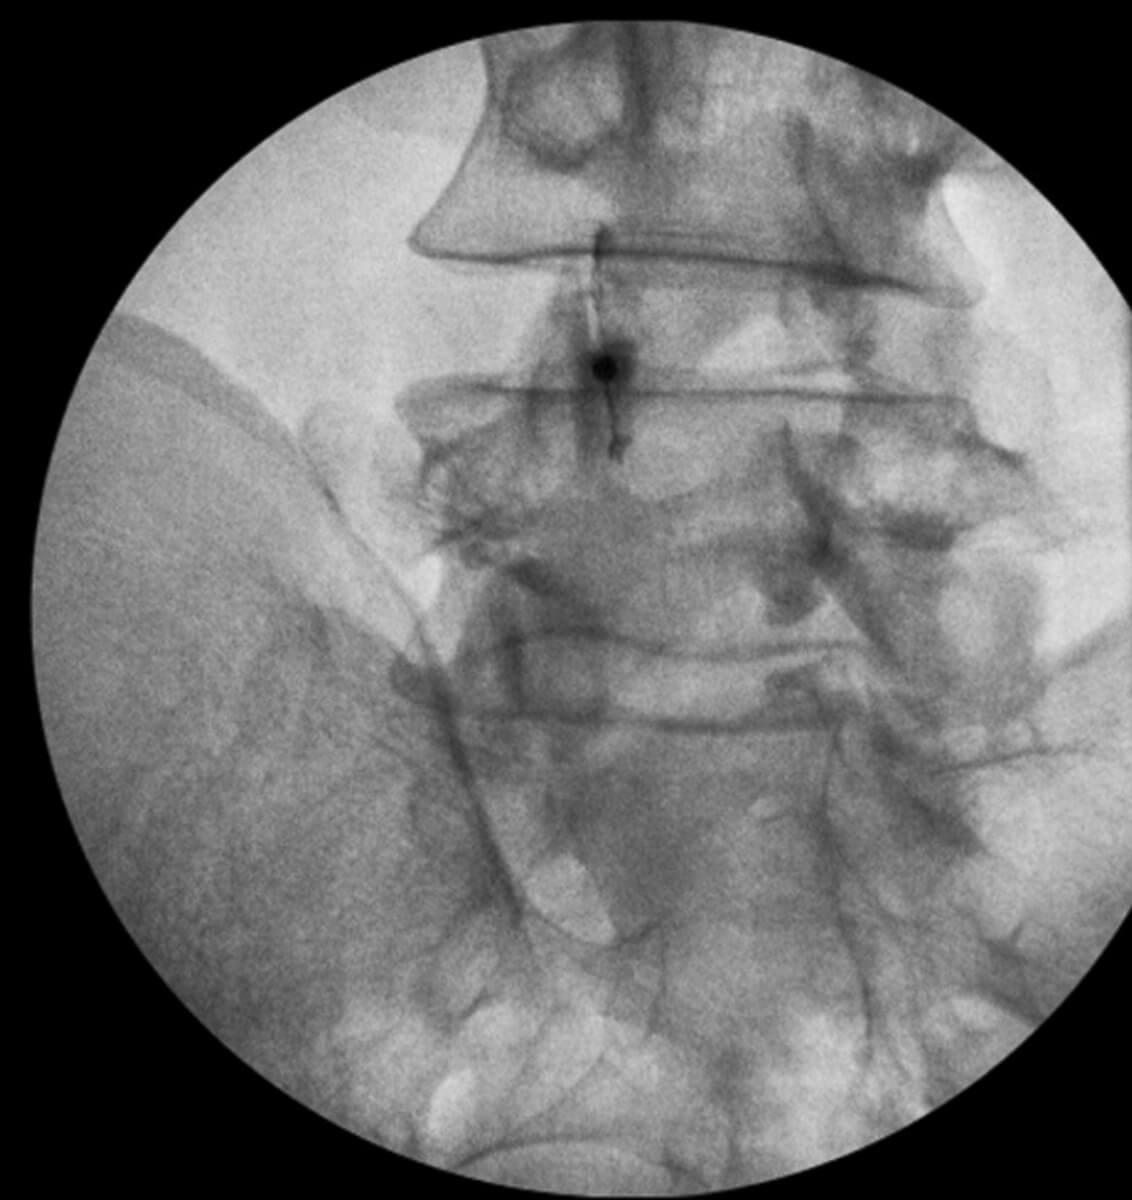

C-arm fluoroscopy is a real-time X-ray imaging system that actively enables dynamic visualization of bony anatomy, joint spaces, and precise needle placement during spinal and sacroiliac joint procedures. Furthermore, clinicians widely regard this technology as the gold standard for spine interventions, because it actively enhances both procedural accuracy and patient safety.

However, when it comes to spine injections and certain deep anatomical targets — such as intraosseous injections — fluoroscopy delivers a level of visualization and accuracy that ultrasound alone simply cannot match. In fact, for these complex procedures, fluoroscopy consistently outperforms other imaging modalities.

- Confirm needle position in real time in multiple planes

- Visualize bony landmarks with exceptional clarity

- Use contrast dye to confirm accurate delivery of biologics or therapeutic agents